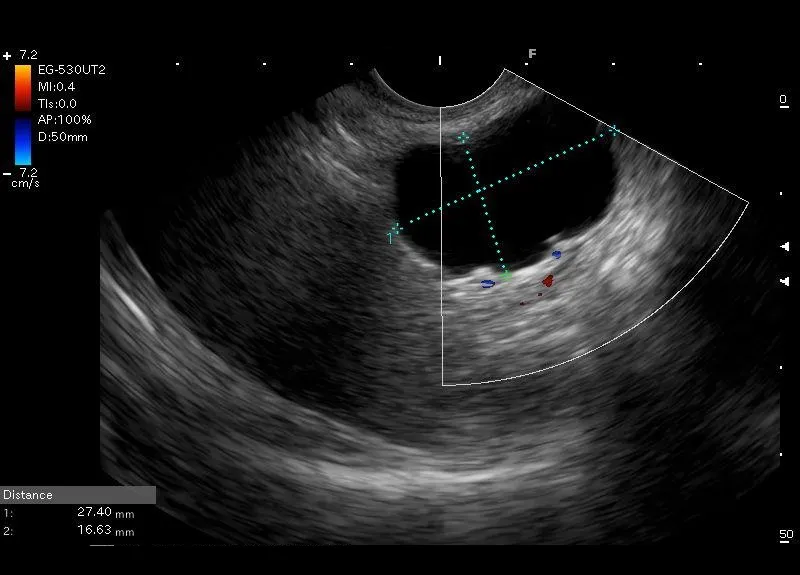

Położona w trzonie trzustki bezechowa przestrzeń o wyraźnie widocznych granicach ( torebka) , bez widocznych w świetle struktur - torbiel trzustki